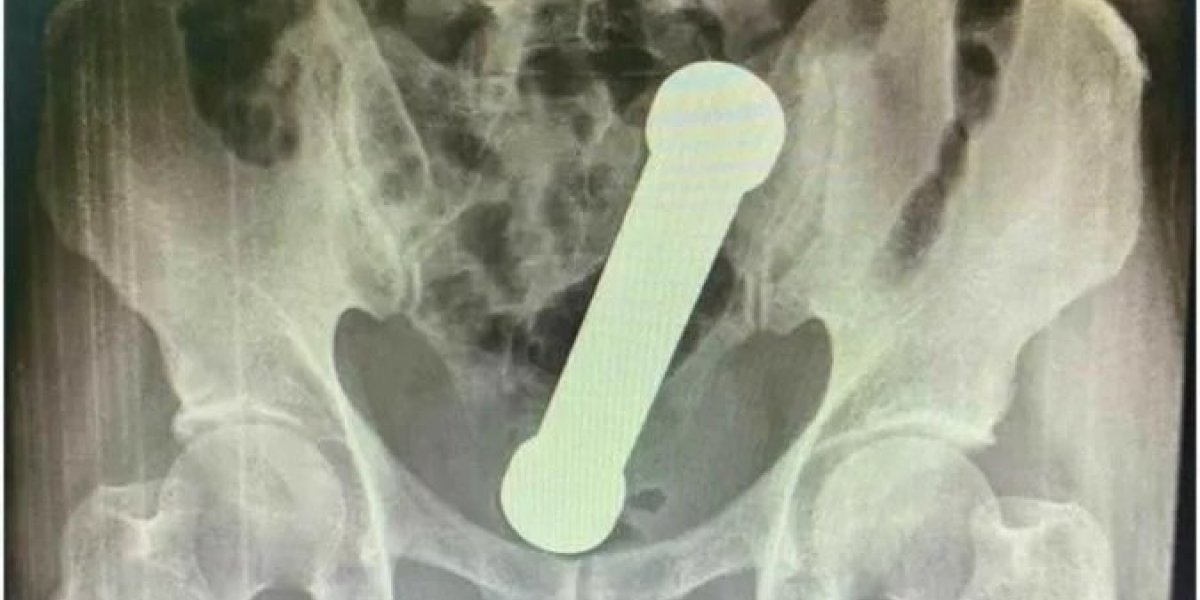

Médicos removem haltere de 2kg do ânus de homem; caso aconteceu em Manaus

Foto: Reprodução / Science Direct

Um caso médico ocorrido na cidade de Manaus, no estado do Amazonas, ganhou as páginas da revista científica Science Direct, especializada em relatos cirúrgicos. Um homem de 54 anos teria chegado a uma unidade de atendimento médico com um haltere (peso de academia) de 2kg no ânus.

O paciente chegou ao pronto-socorro relatando cólicas, náuseas e vômitos, além de interrupção de evacuação há dois dias. Em seguida, o homem foi examinado e apresentou normalidade de todos os sinais vitais. Entretanto, os médicos notaram que o abdômen estava inchado. Com uma nova bateria de exames, foi encontrada, através de uma radiografia, a presença de um 'corpo estranho' na região abdominal, entre a parte terminal do intestino e a parte inicial do reto.